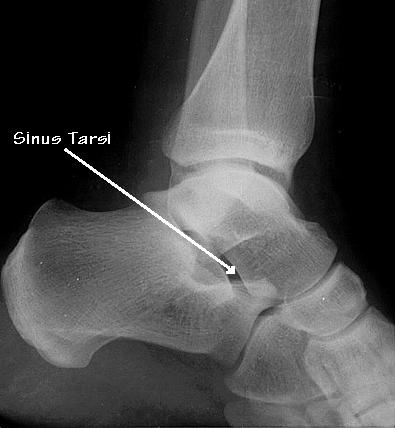

Sinus tarsi syndroom

De sinus tarsi is een tunnel die in de voet tussen de middenvoetsbeentjes loopt

Bij het sinus tarsi syndroom zijn de weefsels in en/of rondom de sinus tarsi aangedaan. Hierdoor ontstaan klachten als pijn, instabiliteit en tintelingen aan de buitenzijde van de enkel/voet.